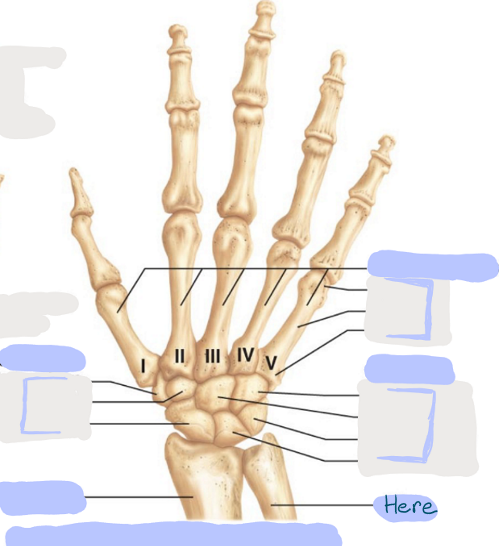

What is this picture of?

Anterior View of the Right Hand

What is here?

Where is the Ulna?

What is here?

Where is the Radius?

What is here?

Where are some of the Carpals?

What is here?

Where are some of the Carpals?

What is here?

Where are the Phalanges?